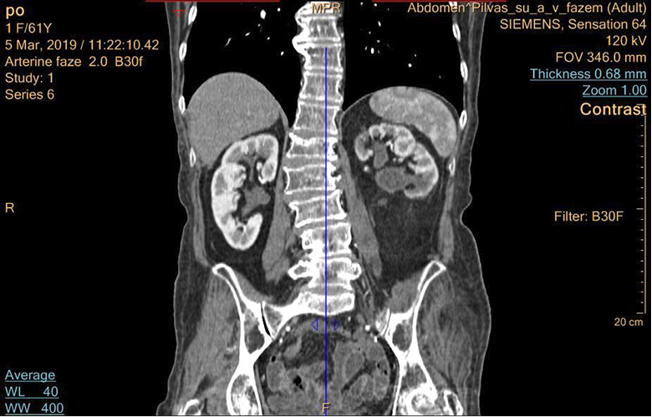

4 pav. Pacientės inkstų KT po operacijos praėjus dviem mėnesiams

Po mėnesio pacientei pašalintas endostentas iš kairiojo šlapimtakio. Pooperaciniu periodu pacientė kairiojo juosmens skausmų nejaučia, šlapinasi gerai. Pacientei likę minimalūs pooperaciniai randai (žr. 3 pav.). 2019-03-05 atlikta kontrolinė KT – kairiojo inksto geldelės prasiplėtimas sumažėjęs iki 19 mm (žr. 4 pav.). Tyrimuose – kreatininas (66 µmol).